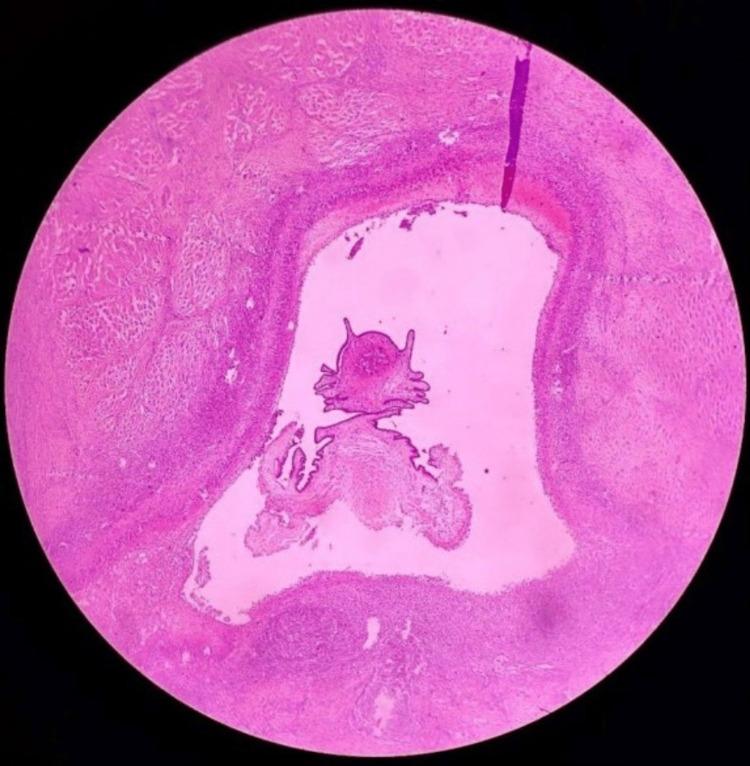

Cysticercosis is a rare condition associated with the development of cysticercus (larval form) of Taenia solium (pork tapeworm), within an intermediate host. Accidental ingestion of infectious eggs is most likely the cause of humans becoming intermediate hosts. The most common site for larval cysts is the central nervous system followed by vitreous humor of the eye, striated muscle, and, in rare cases, subcutaneous and other tissues. Isolated muscular involvement with nonspecific symptoms makes this condition challenging to diagnose. We present an unusual case of cysticercus in the sternocleidomastoid muscle diagnosed with ultrasonography and contrast-enhanced scans, which was subsequently treated with surgical excision and a short course of anthelmintics.

囊尾蚴病是一种罕见疾病,与猪带绦虫(猪肉绦虫)的囊尾蚴(幼虫形式)在中间宿主体内发育有关。意外摄入感染性虫卵很可能是人类成为中间宿主的原因。幼虫囊肿最常见的部位是中枢神经系统,其次是眼玻璃体液、横纹肌,在罕见情况下还有皮下组织和其他组织。孤立的肌肉受累伴非特异性症状使得这种疾病的诊断具有挑战性。我们报告一例罕见的胸锁乳突肌囊尾蚴病例,通过超声检查和增强扫描得以诊断,随后接受了手术切除和短期驱虫治疗。